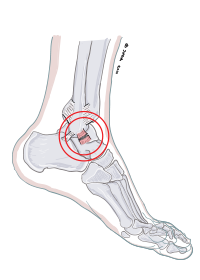

Ligamentskada fotled

I samband med en kraftig fotledsstukning går ligamentet på utsidan foten av.

Skadan läker oftast problemfritt men efter flertalet stukningar kan dock ligamentet som skadas läka med förlängning och en instabilitet uppstår i fotleden.

Följden blir smärtor och att man lätt stukar sig.

En instabilitet I fotleden behandlas i första hand med fysioterapi.

Vid kvarstående besvär kan man kirurgiskt strama upp fotleden med olika metoder.

Ofta förankras de uppstramade ligamenten med stygn genom benkanaler.